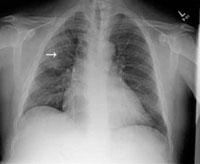

- Chest x-ray film shows right upper lobe infiltrate with minimal pleural effusion (FIGURE 2).

FIGURE 2

Posterior-anterior chest x-ray

The patient has consolidation in the right upper lobe with minimal pleural effusion on the right side.